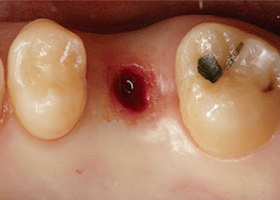

傳統植牙方式是屬於”手術行為”,病患需接受局部麻醉,再以劃開牙肉、翻瓣、鑽孔的將植體植入牙齦內的齒槽骨中。 這樣的手術方式,療程時間較長,且傷口較大,所產生的疼痛、出血腫脹以及傷口復原的時間也相對較長。